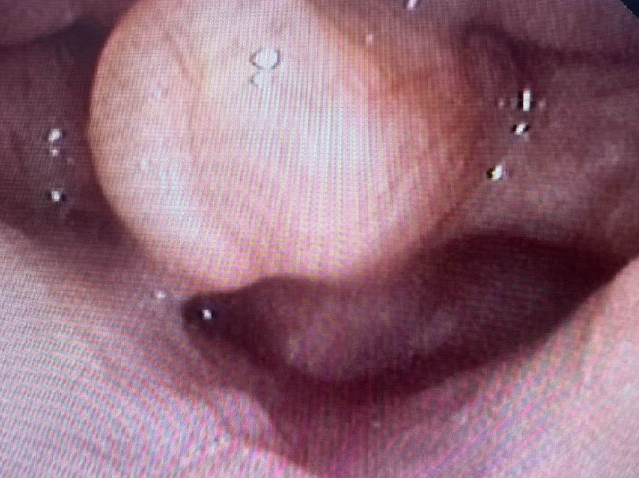

岳阳市中医医院儿科主任雷东方接诊患儿时,根据家长的描述,认真细致地听诊、体查后,认为宝宝发出的“呼噜呼噜”的声音,可能是喉软骨软化症。随后排纤支镜检查。果不其然,患儿镜下会厌软骨明显软化、卷曲、倒伏,证实了这一诊断。

↑↑↑正常(左)与喉软化症(右)对比图↑↑↑